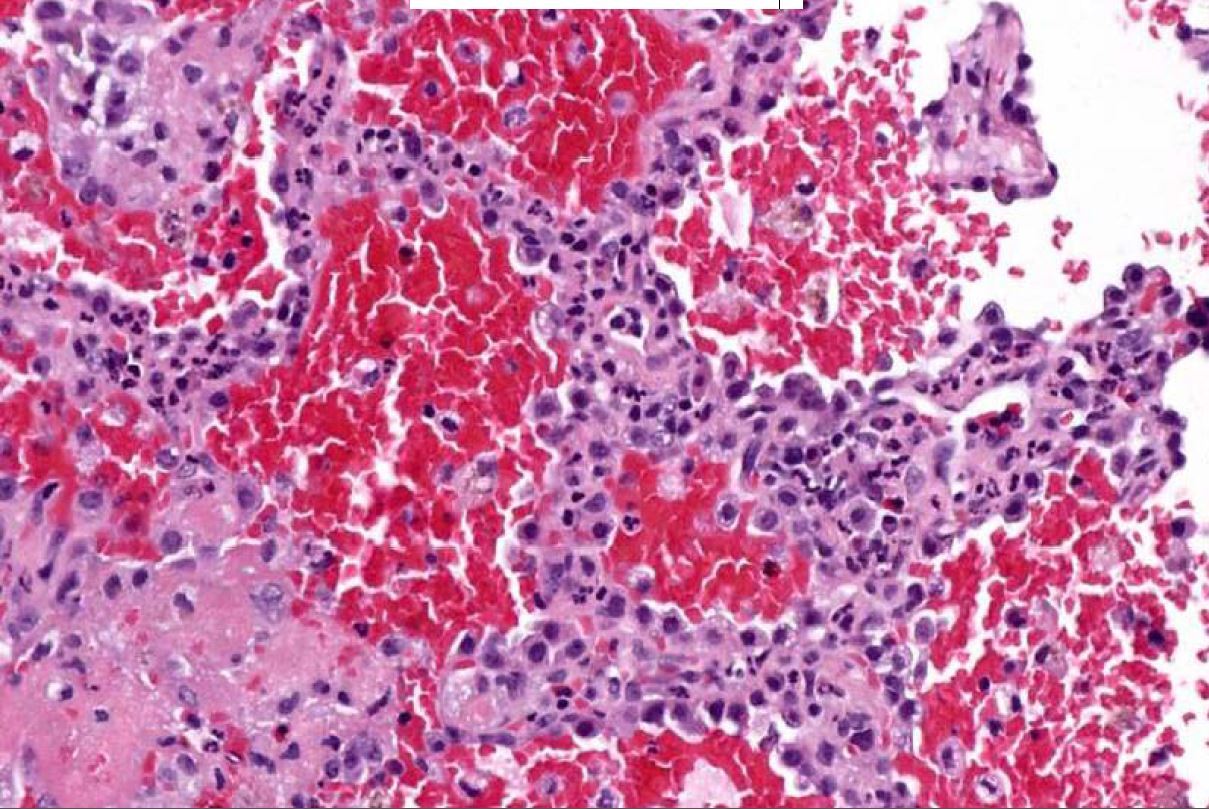

If you see a lung tumor with this appearance, what is diagnose?

Pulmonary blastoma (fetal adenocarcinoma)

Primitive glands and stroma, resembles fetal lung